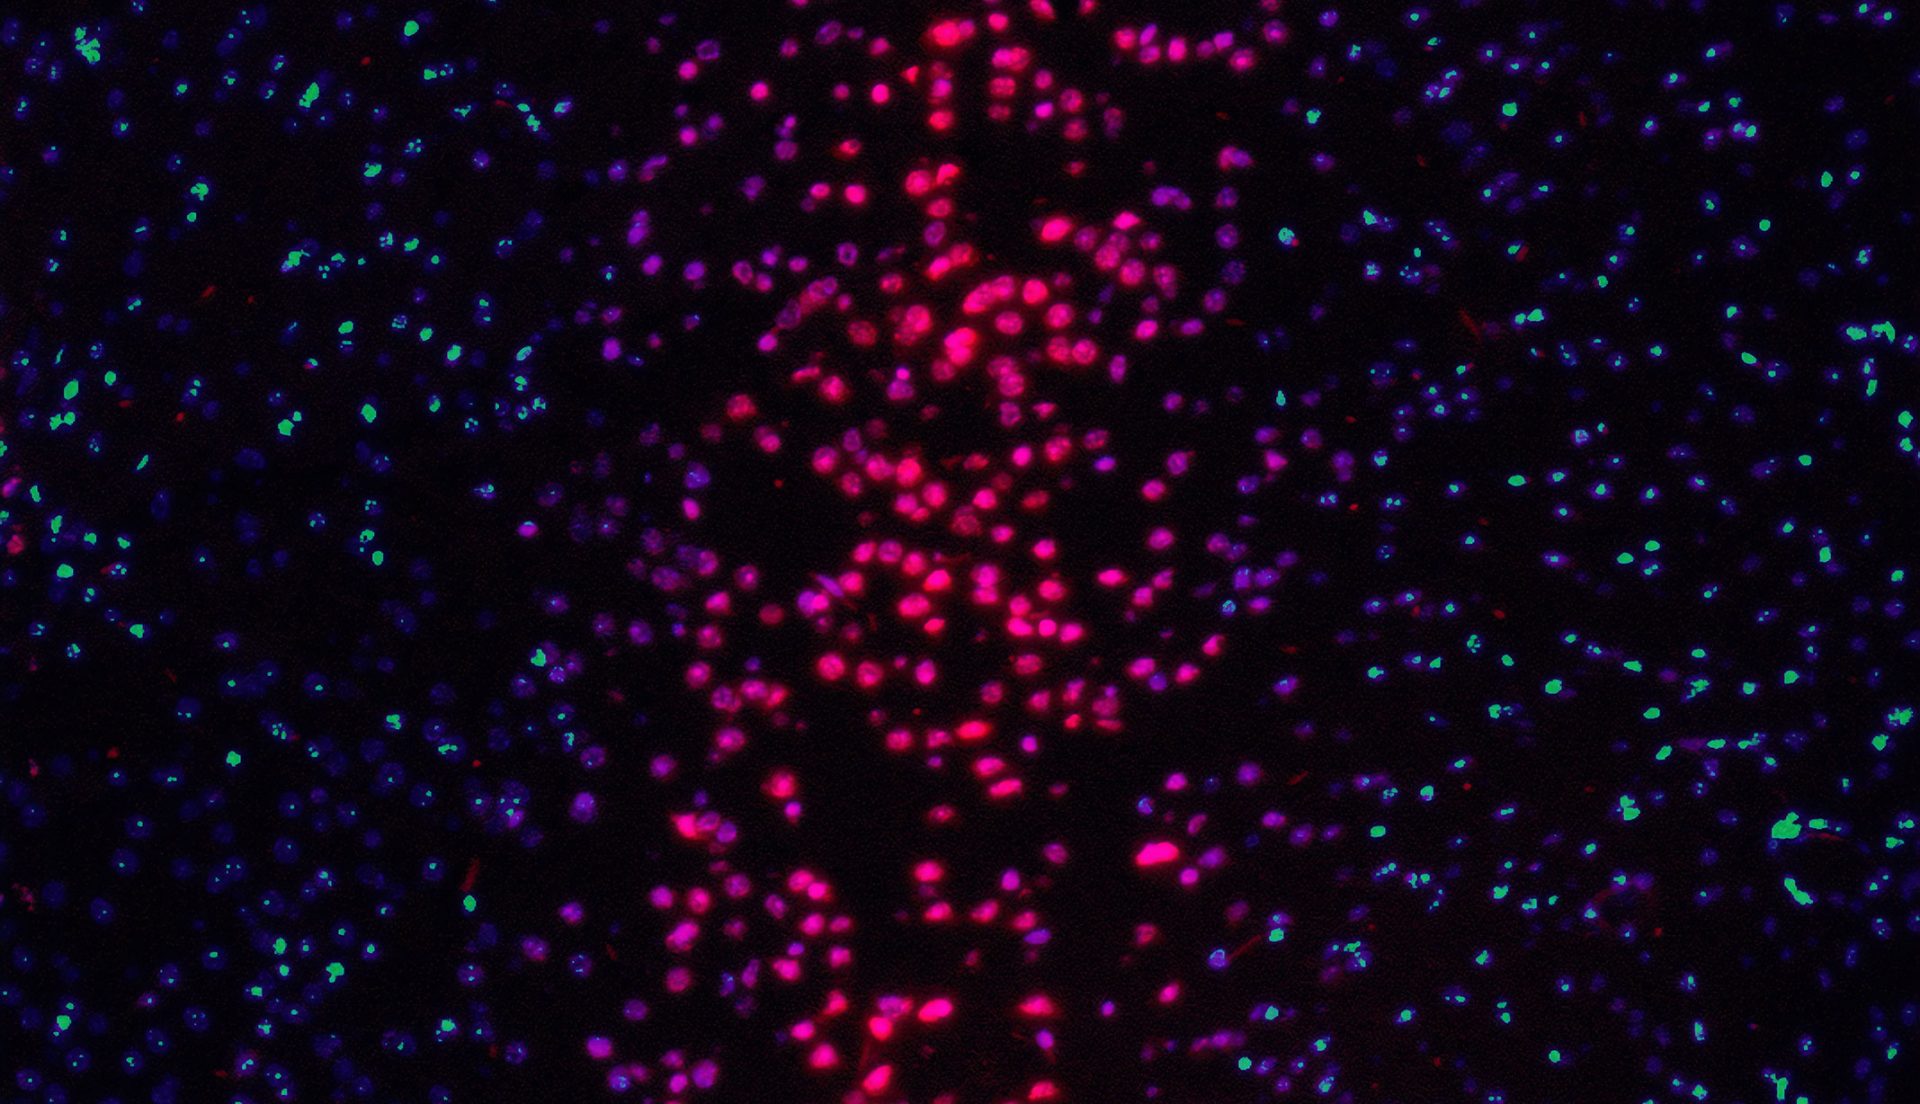

- Digital slide scanning and quantitative image analysis including analysis of TMA sections